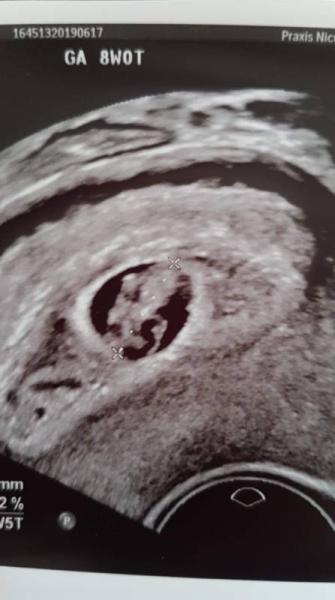

Hallo ihr Lieben! Ich bingabz neu hier im Forum und habe gleich mal eine Frage an euch. Ich bin laut Rechnung heut bei 8+1. Gestetn bei 8+0 hatte ich einen Termin beim FA. Momentan sieht es bei mir wie folgt aus: Der Embryo ist bei 7+5, hinkt also 2 Tage zurück. Problem ist, dass die komplette FH von einem Hämatom umringt und zudem deutlich zu klein ist (laut Messung entspricht sie einer FH bei 7+0). Der Dottersack dagegen ist immer noch so groß, wie bei 6+3. Ich bin total Rat los und traurig. Auch die Ärtzin heute, hat mir nicht allzu große Hoffnungen machen können. Hatte das jemand von euch auch schon? Was kam dabei raus? Ging es bei jemandem gut aus? Vielen Dank im Voraus! LG CurlySue8

Bild zu 8+0, Embryo OK, FH zu klein, Dottersack zu groß - Forum für Januar - Mamis

Danke dir, für die lieben Worte. Dass mit den 2 Tagen zurück datiert brim Embryo ist allgemein nichts ungewöhnliches. Ist jetzt meine 4m Schwangerschaft und das kam eigtl bei jeder mindestens 1x vor. Mein 2ter wurde allgemein mal glatte 3 Wochen zurück datiert. Das große Problem ist wohl die Feuchthöhle. Sie liegt von der Entwicklung bereits eine Woche hinter dem Embryo. Auf dem Biöd sieht man das denke ich recht deutlich. Er ist jetzt schon am Anschlag. Normal sollte er sich darin frei bewegen können. Dass es am Winkel liegt, denke ich nicht, da es mittlerweile von zwei verschiedenen FA bestätigt wurde. Blöd ist nur, dass keiner irgendeine klare Aussage trifft. Immer nur so schwammiges drum herum. Das ist eigtl das, was mich am meisten belastet, da ich einfach nicht weiß, woran ich bin :-( Ich wünsche dir alles Gute für heute und wünsche dir, dass alles in Ordnung ist